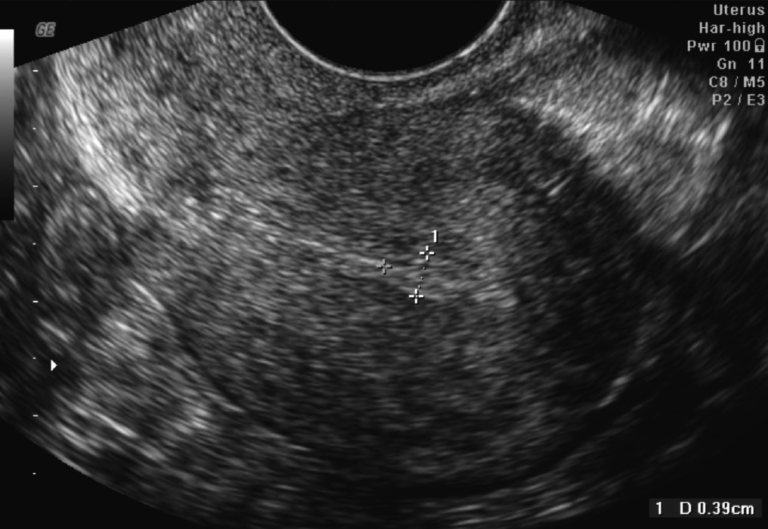

Transvaginal ultrasound image showing thin endometrial lining measuring approximately 5 mm

Transvaginal ultrasound demonstrating a thin endometrial lining measuring approximately 5 mm.

During fertility treatment, especially IVF, we measure endometrial thickness via ultrasound to determine whether the uterine environment is optimal for implantation.